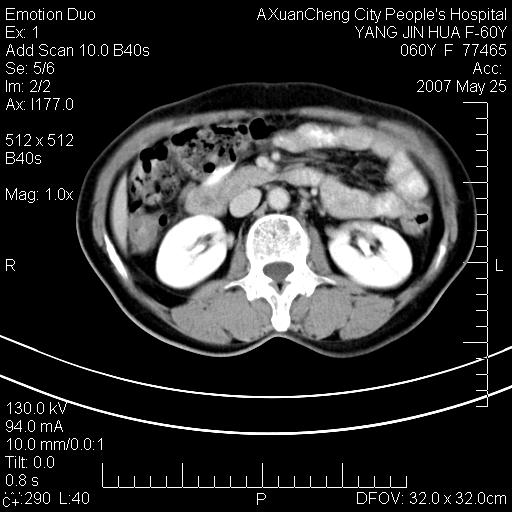

发现左侧腰背部包块40余年,逐渐长大,质软,局部表面可见扩张的血管影

左背部皮下良性肿瘤,密度不均,边界不清,内有脂肪、钙化,增强扫描无明显强化,血管平滑肌脂肪瘤?进一步诊断有困难,建议穿刺活检。

左侧背部皮下混杂密度肿块,结构较疏松,边缘欠光整,内有多发斑点状钙化,考虑:皮下血管瘤。

血管平滑肌脂肪瘤,支持!另应详细了解病史,待除外骨化性肌炎。

1.考虑左腰部皮下平滑肌脂肪瘤可能性大;

2.位置特殊,不除外畸胎瘤及错构瘤可能;

3.另骨化性肌炎应在考虑范围之内,请追问病史;